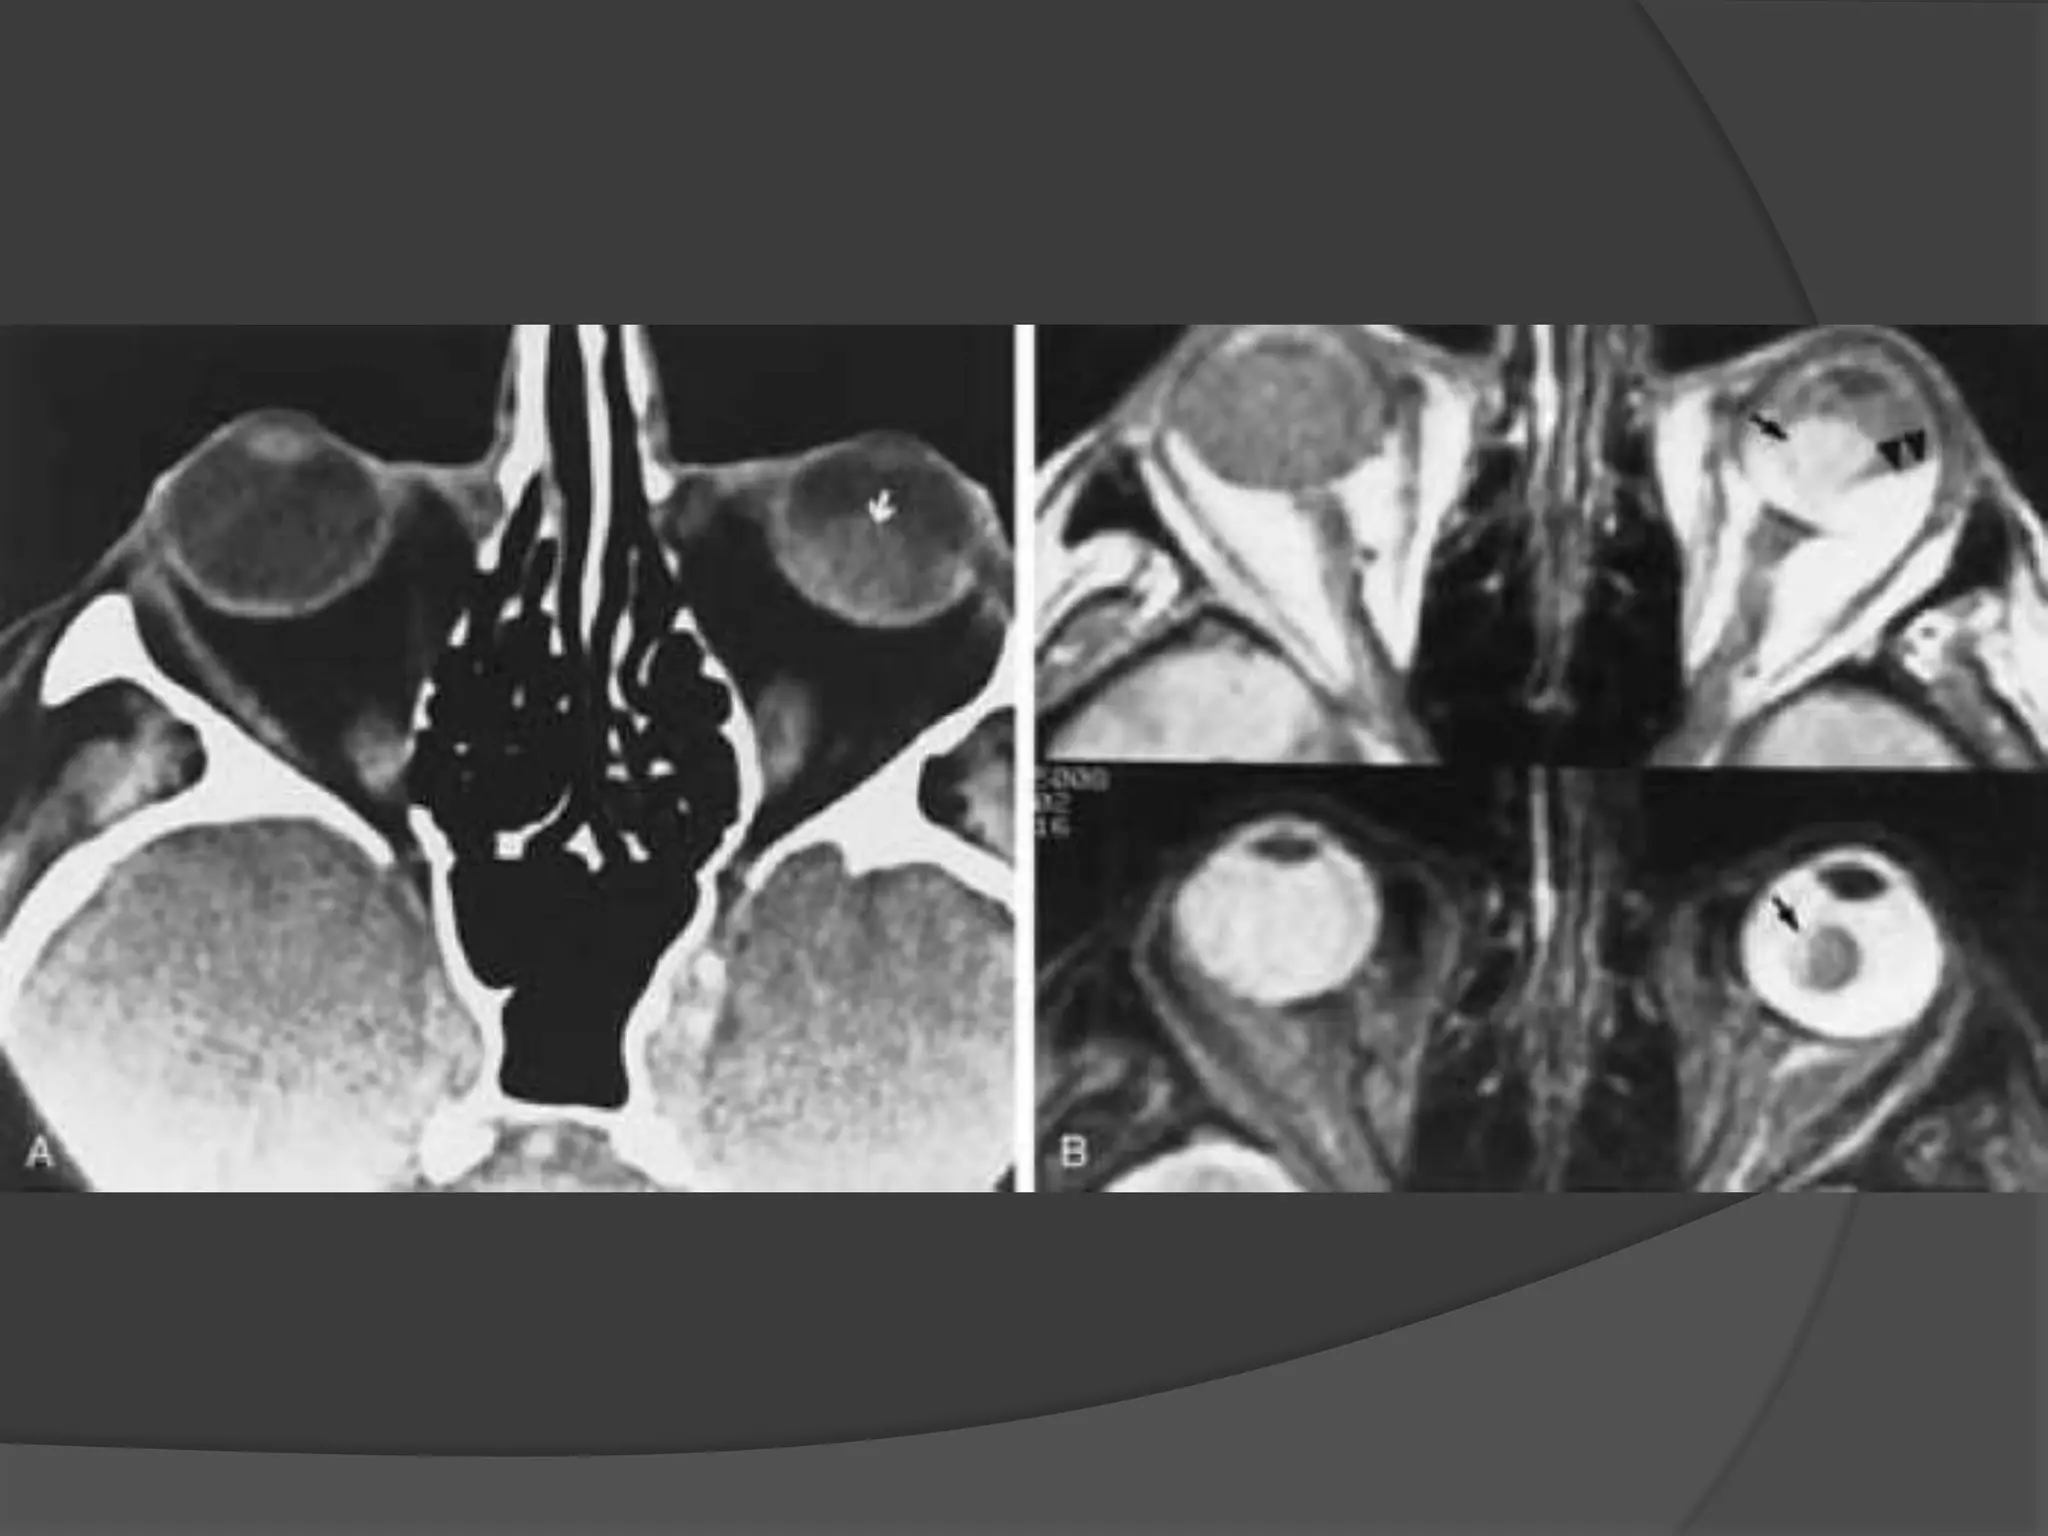

• #30 ROP. A, Axial CT scan shows increased density of the globes and left microphthalmos. B, Axial PW MR image shows hyperintensity of both globes, presumably caused by subretinal hemorrhage. Note the retrolental abnormal tissues (arrows) and detached retina (curved arrow). C, Axial T2-weighted MR image shows hyperintensity of the globes and abnormal retrolental soft tissues (arrows). Note the detached retina (curved arrow) and the layered acute hemorrhage in the right subretinal space (arrowhead ).

• #33 Coats’ disease. A, Axial CT scan shows generalized increased density of the left globe caused by bullous retinal detachment. The leaves of the detached retina are faintly seen, as shown by the arrows. B, Axial PW MR image shows hyperintensity of the left globe caused by subretinal lipoproteinaceous effusion. Note the leaves of the detached retina (arrows). C, Axial T2-weighted MR image shows the detached retina (arrows).